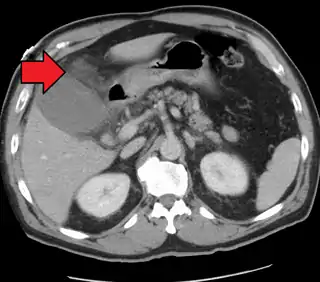

Colecistitis aguda como se ve en la TC.Obsérvese la acumulación de grasa alrededor de la vesícula biliar agrandada. | ||